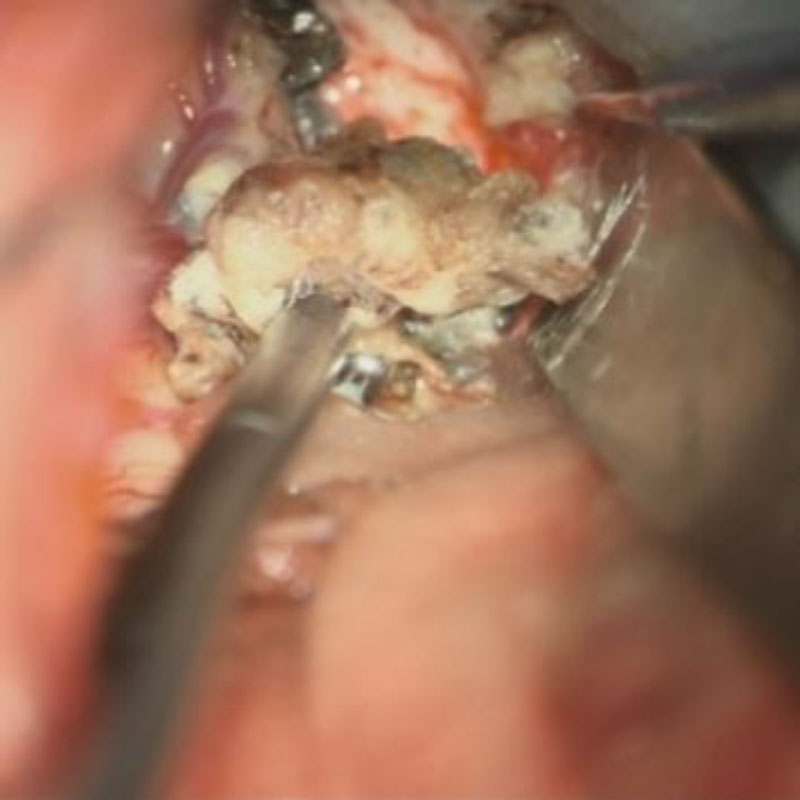

手術写真

手術中